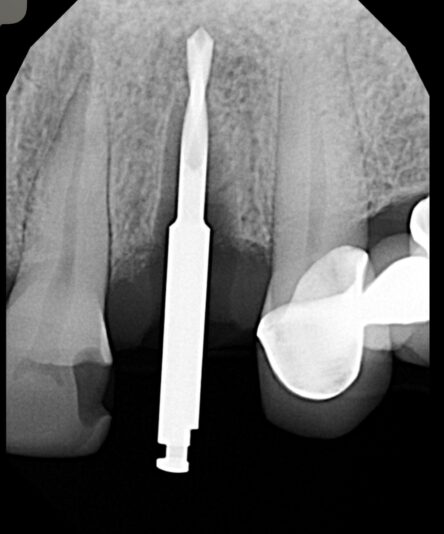

When placing implants, taking a PA X-ray of the pilot drill is a crucial step that’s often overlooked. This simple check can save you from a lot of headaches down the line.

By taking a PA X-ray after placing your pilot drill, you can immediately assess:

• Parallelism to adjacent teeth or implants.

• Proper alignment within the bone.

If you notice angulation issues, the good news is that they’re easily corrected at this stage. You can use a lance drill to adjust the path before moving to wider drills. Once you progress past the pilot stage, corrections become much harder and risk compromising the implant site.